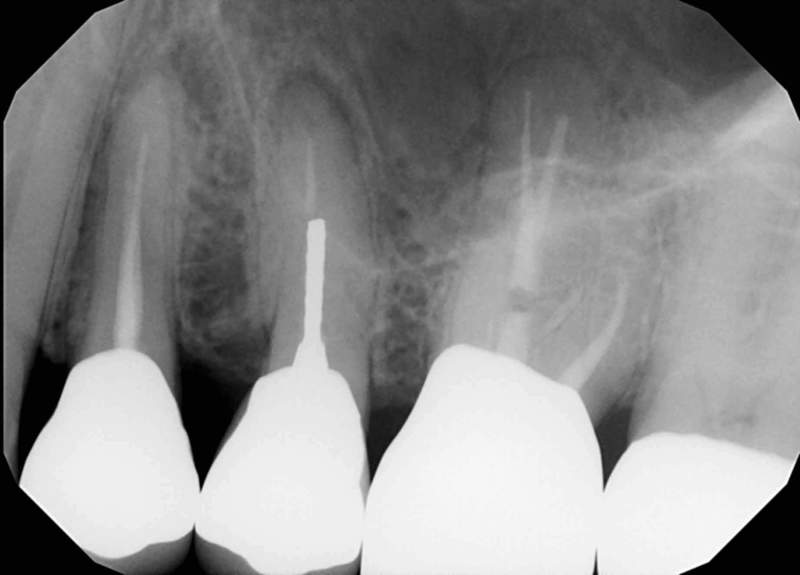

Before & After bone grafting – implants are now possible instead of dentures: